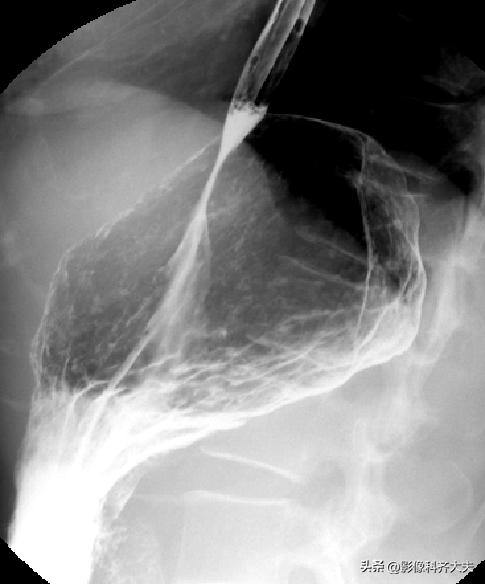

胃双对比相(仰卧右前斜位)

胃双对比相(仰卧左前斜位)